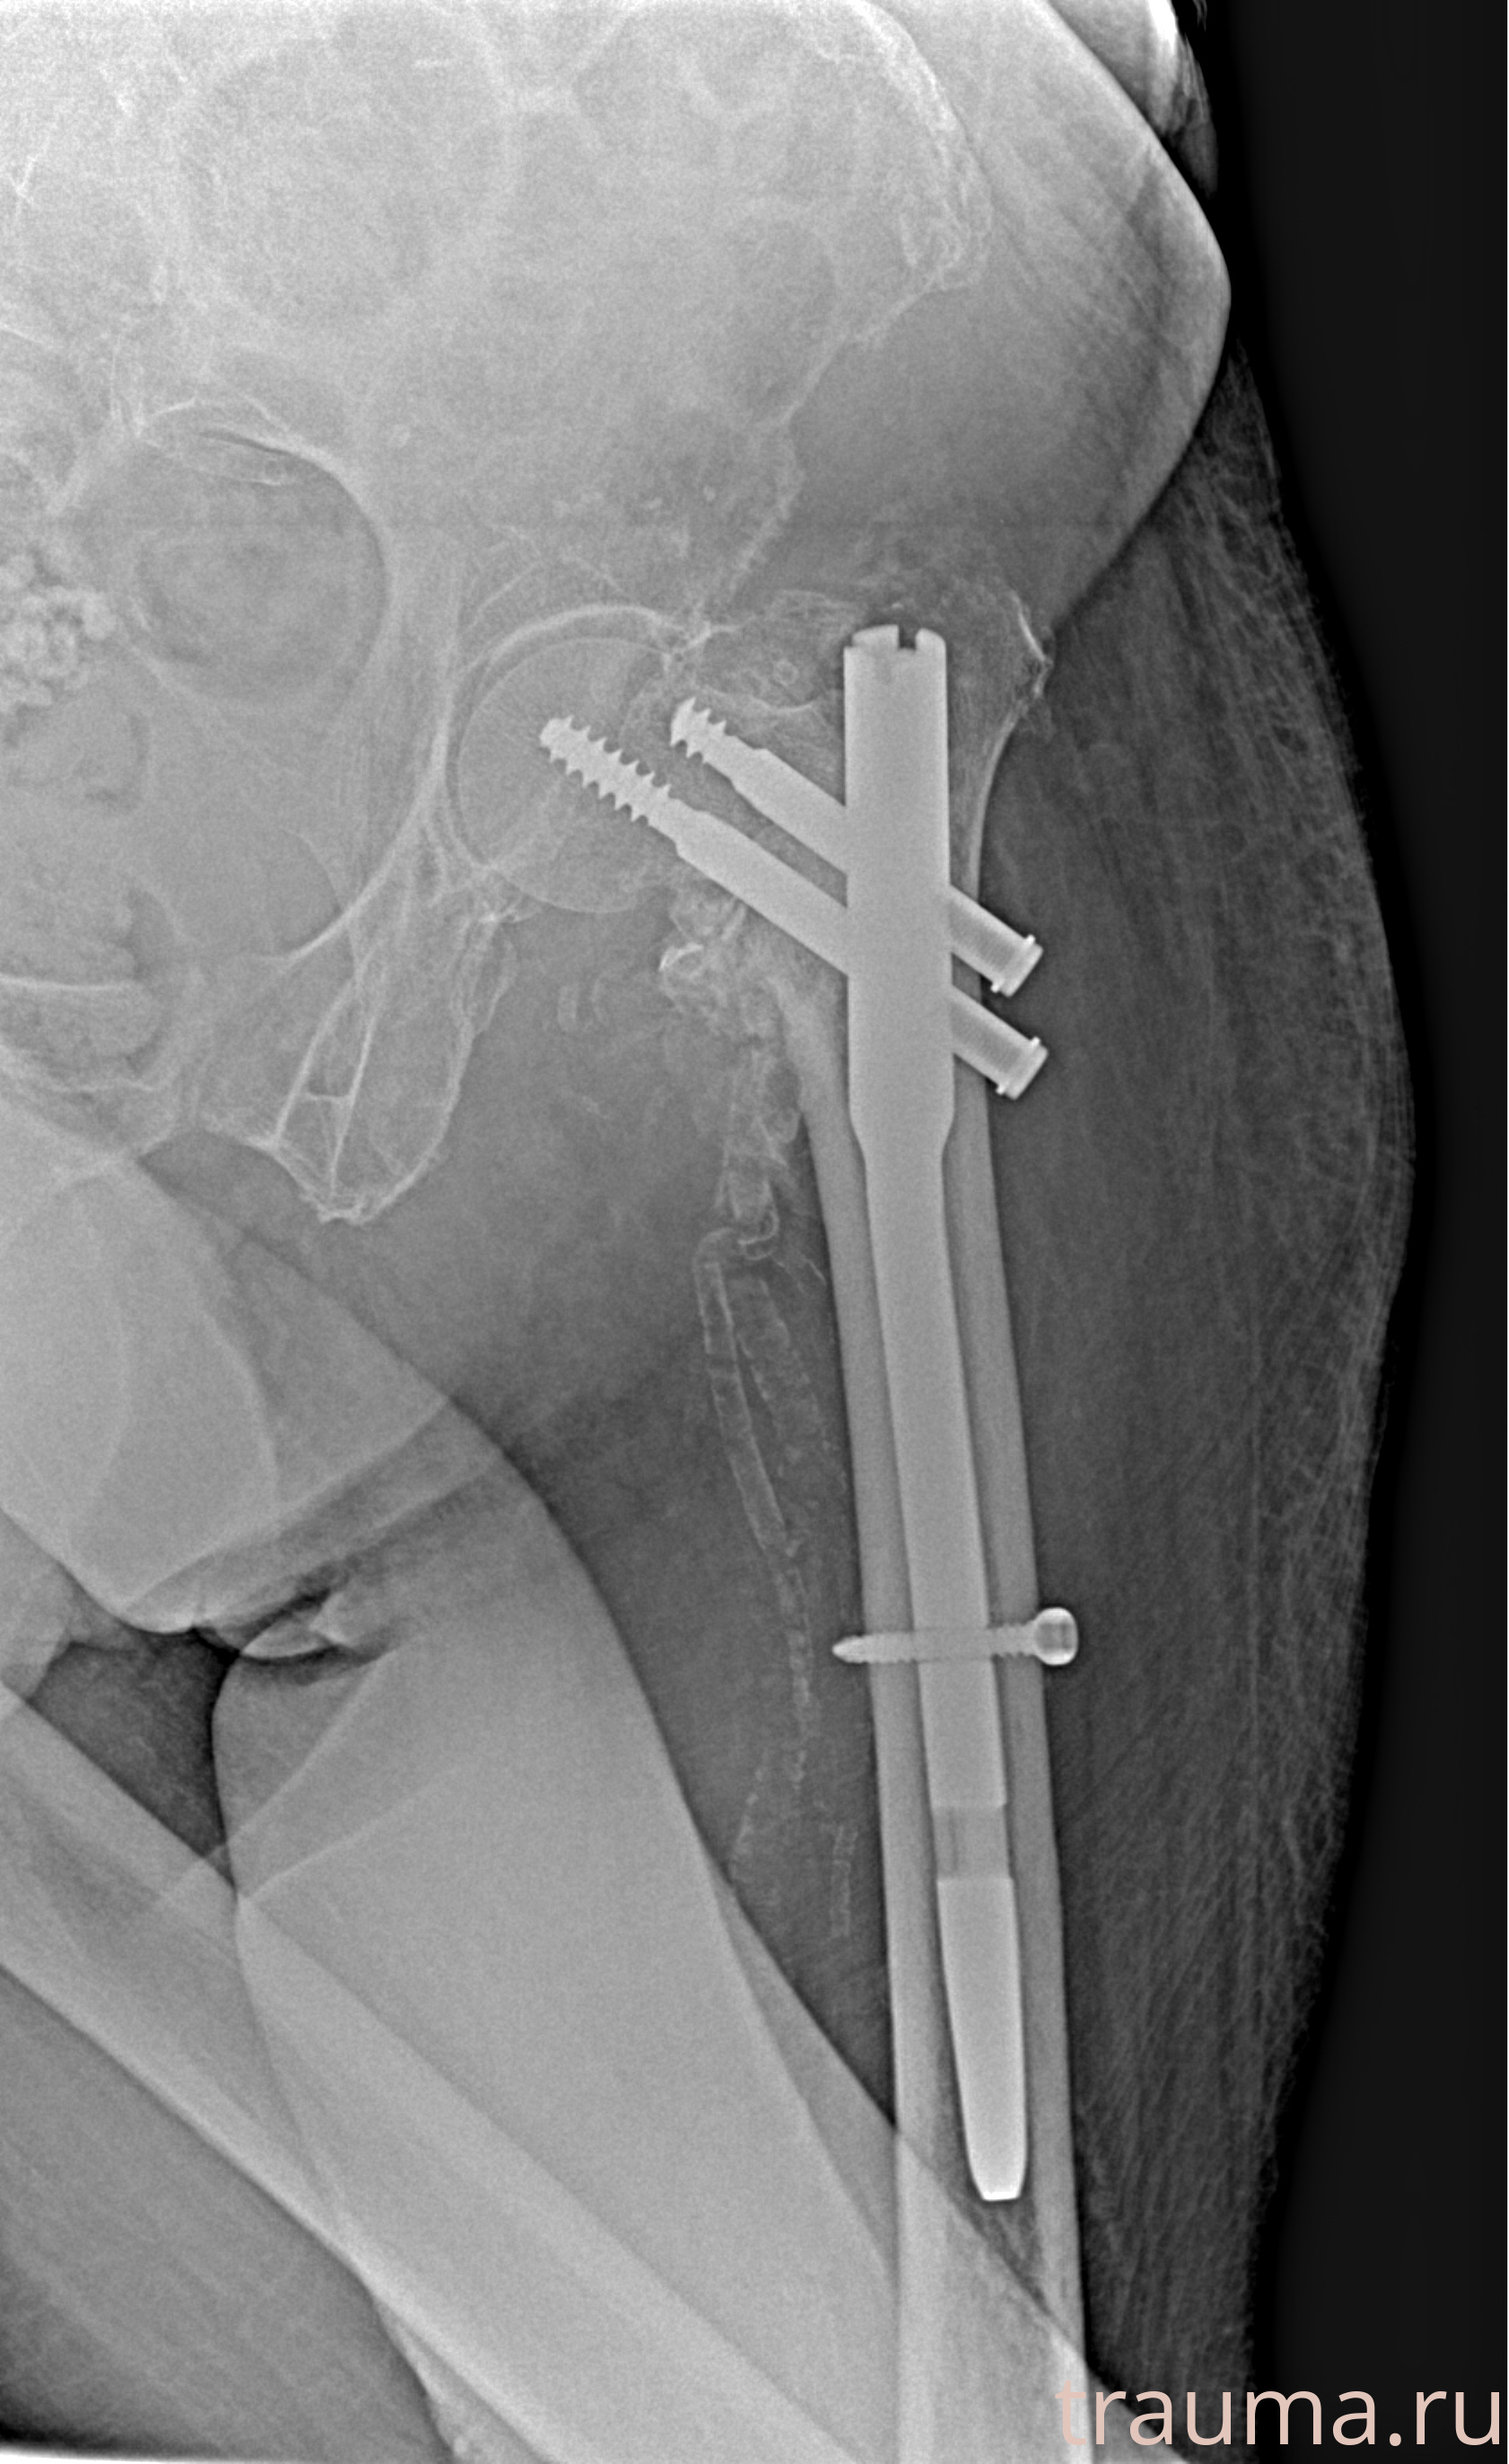

Рентгенограммы

Рентген на дому: по вашему адресу приезжает врач-рентгенолог, травматолог-ортопед с мобильным рентгеновским аппаратом, проводит диагностику травмы или заболевания, делает необходимые рентгенограммы, дает рекомендации по дальнейшему лечению. Получить качественные снимки в домашних условиях возможно благодаря уникальной методике, разработанной МосРентген Центром для института  Склифосовского